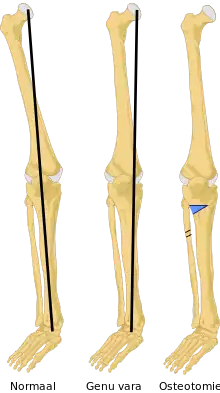

Le genu varum est une déformation (un trouble orthostatique) du membre inférieur, qui siège dans l'articulation du genou, mise en évidence après avoir demandé au sujet debout de coller ses chevilles l'une à l'autre (les malléoles médiales se touchent) et en observant l'absence de contact entre les deux genoux.

On dit que « les jambes sont arquées ». Il est possible d'objectiver le genu varum par la mesure de la distance entre les faces médiales (les faces internes) des genoux.

Le genu varum est un des facteurs qui favorisent l'arthrose du genou (l'arthrose du compartiment fémoro-tibial médial du genou).